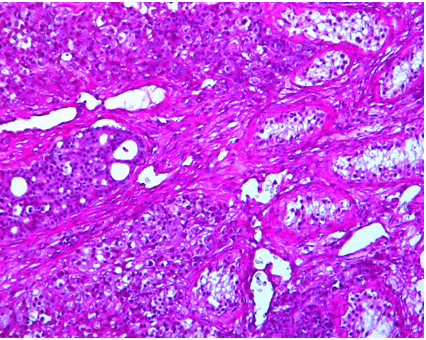

The patient had a left inguinal orchidectomy, the histology of which confirmed an adenocarcinoma tumor infiltrate of the left testis with vascular as well as intra ductal extension of the neoplastic cells (Figure 2).

Figure 2: Residual seminiferous tubules with interspersed islands of the metastatic adenocarcinoma (H&E stain, x100).